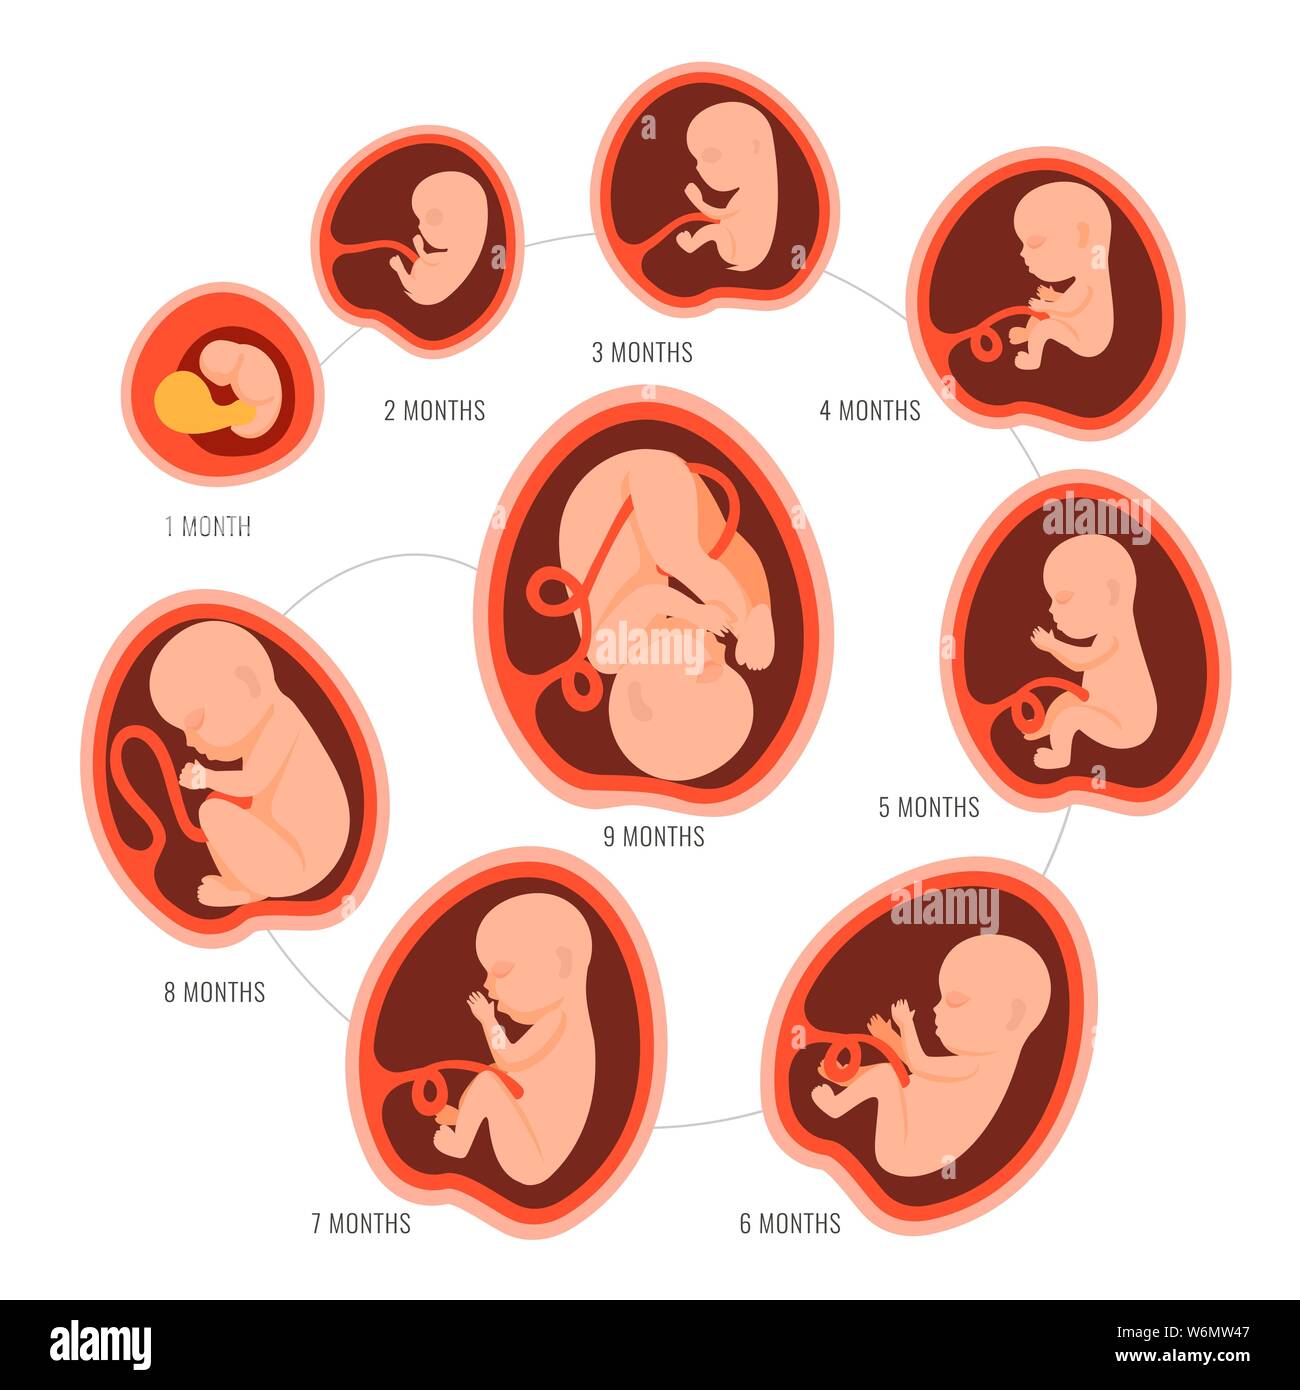

Looking for captivating what does a 2 month old fetus look like images? All, in collaboration with felix.edu.vn, presents a curated selection. Dive into the details for more.

what does a 2 month old fetus look like

Posts: what does a 2 month old fetus look like